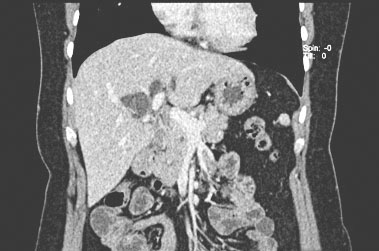

术前PTCD造影:引流管在位,可见扩张的残余囊肿,间置空肠代胆总管区域显影不良。

术中探查:肝门区粘连严重,残余胆管囊肿-间置空肠端侧吻合口至间置空肠-十二指肠端侧吻合口约5cm,间置空肠盲端长约5cm,原胆肠吻合口直径约1.5cm。肝门部原吻合口附近肝总管及左右肝管均有残余的胆管囊肿。

手术过程:拆除原胆肠吻合和空肠十二指肠吻合、切除间置空肠,切除残余胆管囊肿。修补十二指肠原肠肠吻合口处肠壁。探查左右肝管、取净结石。行肝门胆管-空肠Roux-en-Y吻合,吻合口直径约2.5cm。